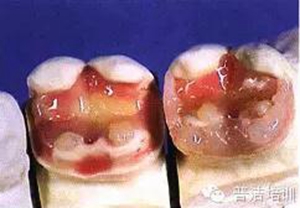

八、在可卸帶型上的樹脂嵌體,拋光

九、準(zhǔn)備口內(nèi)戴入

十、試戴樹脂高嵌體